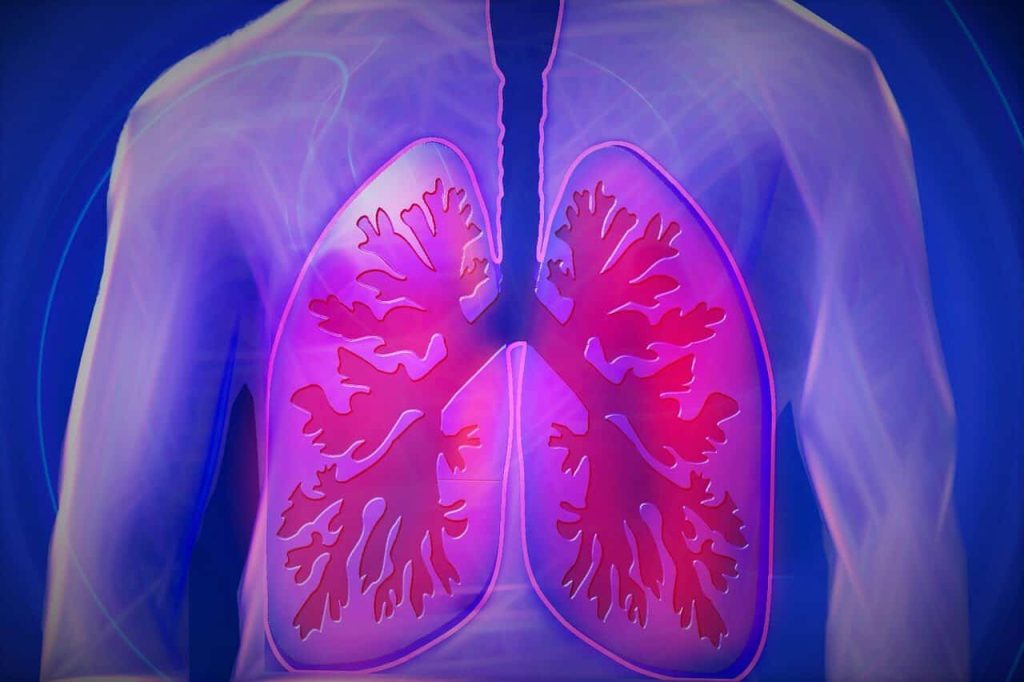

La Fibrosis Quística es una enfermedad hereditaria, congénita y crónica que afecta a las vías respiratorias y digestivas.

Cada 8 de septiembre se conmemora el Día Mundial de la Fibrosis Quística, una enfermedad hereditaria, congénita y crónica que afecta a las vías respiratorias y digestivas, resultado de una alteración genética. La fibrosis quística es una enfermedad poco común pero significativa, que requiere atención y apoyo continuo.

Los síntomas de la fibrosis quística pueden variar de una persona a otra, pero comúnmente incluyen: tos persistente y producción abundante de flema, dificultad para respirar debido a infecciones pulmonares recurrentes, problemas digestivos, como dificultad para absorber nutrientes y malnutrición, sudor salado y presenta un crecimiento deficiente en niños.

El tratamiento de la fibrosis quística es multidisciplinario y busca aliviar los síntomas y mejorar la calidad de vida de quienes la padecen a través de terapia respiratoria para limpiar las vías respiratorias; medicamentos para reducir la inflamación y prevenir infecciones pulmonares; suplementos nutricionales para abordar problemas digestivos; fisioterapia y ejercicio para mejorar la función pulmonar y/o apoyo psicológico y emocional para pacientes y sus familias.